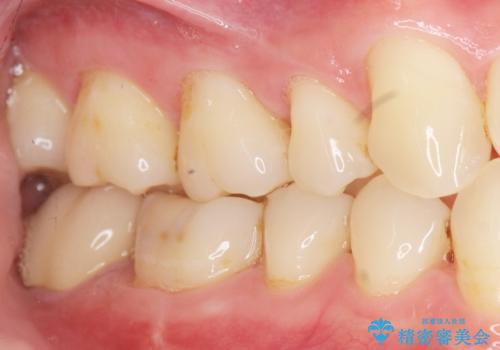

精査したところ、右下の一番奥の歯(右下7)に歯肉縁下に及ぶ深いう蝕を認めました。

神経がない歯であり痛みが出ないことから、自覚症状がほとんどなくう蝕が大きく進行してしまったと考えられます。

銀歯を除去し、歯周外科処置(右下7遠心の骨整形及びディスタルウェッジ)を行った後にメタルボンドクラウンによる補綴を行いました。

隣の歯(右下6)はセラミックインレーで修復しました。